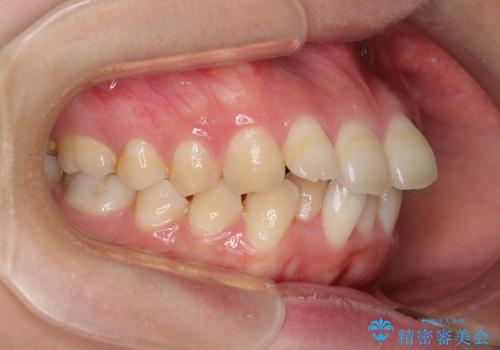

- 上の前歯の出っ歯とでこぼこの歯並びを気にして来院された患者様です。

口元を積極的に引っ込めるために、上下左右の小臼歯4本を抜歯することとしました。